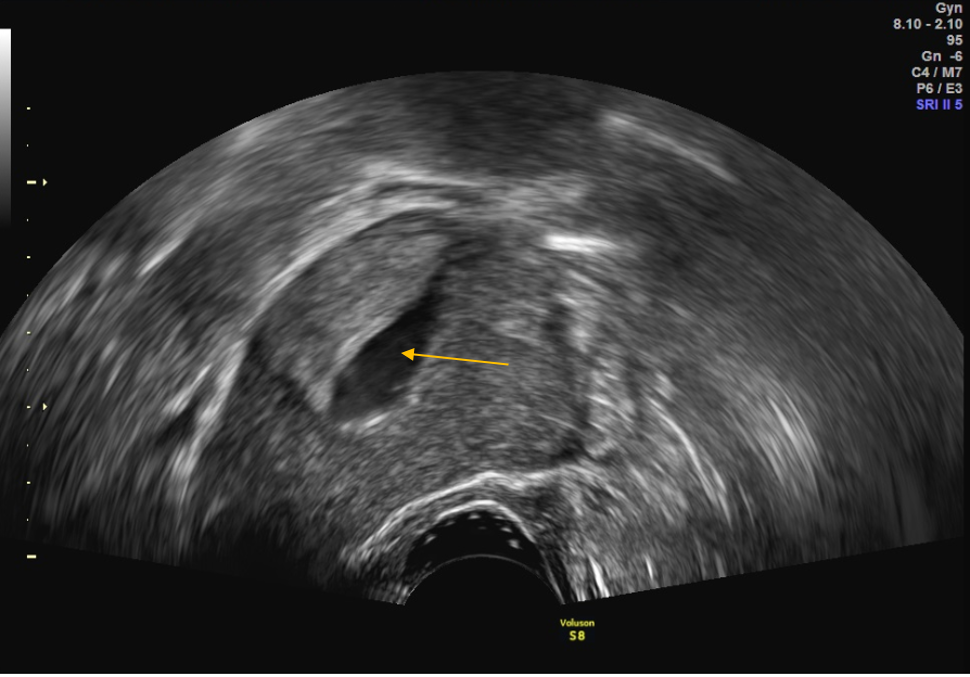

Cavumdarstellung in der Hydrosonographie

HyCoSy mit Kontrastmittelaustritt Tube rechts